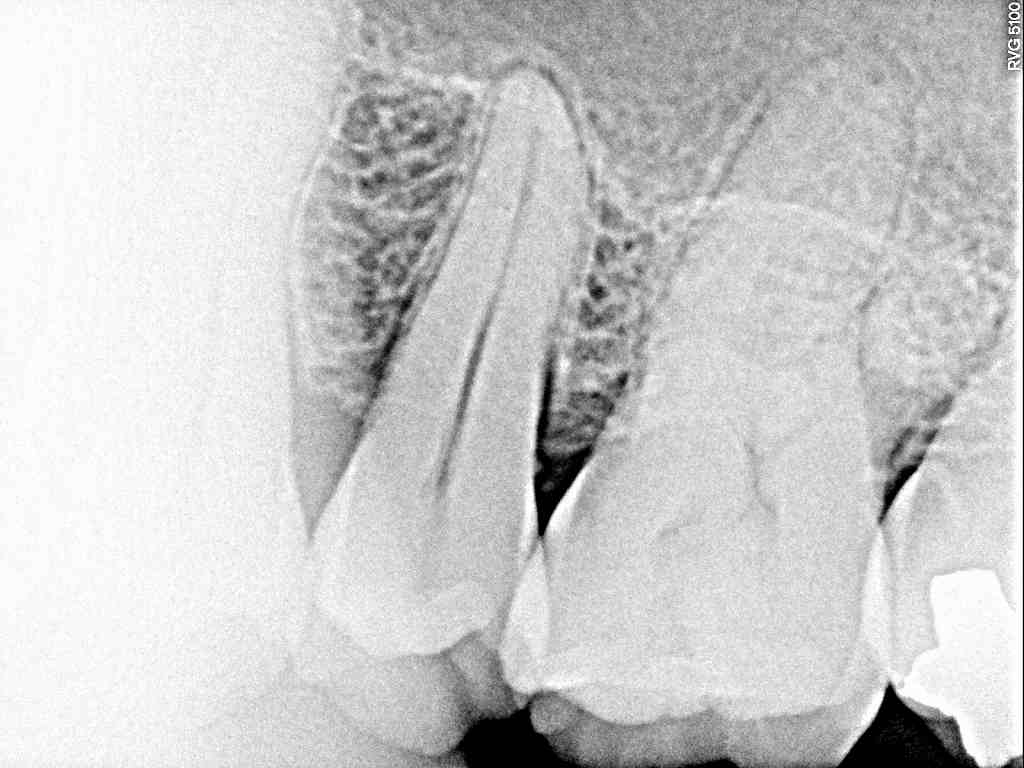

レントゲンです

6番は神経に作用するような大きな虫歯は感じにくいです

奥から2番目の7番の歯が原因ですが、、

レントゲンにてもさほど大きな虫歯には感じられません

レントゲンにても分かりにくかったのでCTにて精査していきました